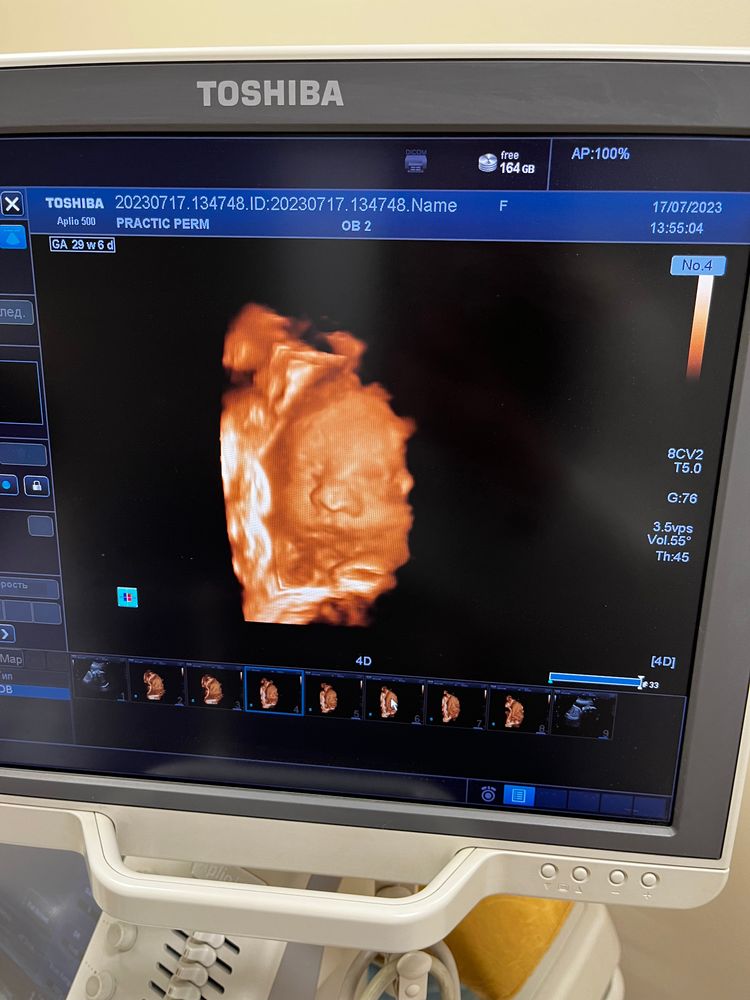

Наша принцесса🥰

УЗИ, КТГ, доплерЗавтра будет ровно 30 неделек, уже вышла в декрет. Малышка ооочень активная, живот перекручивает вдоль и поперек, по сегодняшнему узи 1370г в головном предлежании🥰

все узи открывала ротик, махала ручками, стучала в датчик😄

очень ждем тебя, наша девочка❤️